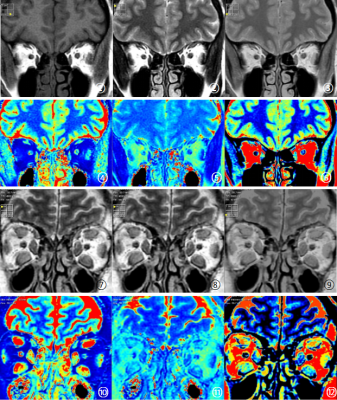

Figure1 Synthetic MRI images of experimental group and healthy controls

① to ⑥ are the schematic diagram of healthy controls synthetic MRI images, which are T1WI, T2WI, PDWI, T1MAPPING, T2MAPPING and PDMAPPING, respectively ⑦ -Synthetic MRI images of the experimental group were consistent with those of the healthy controls.